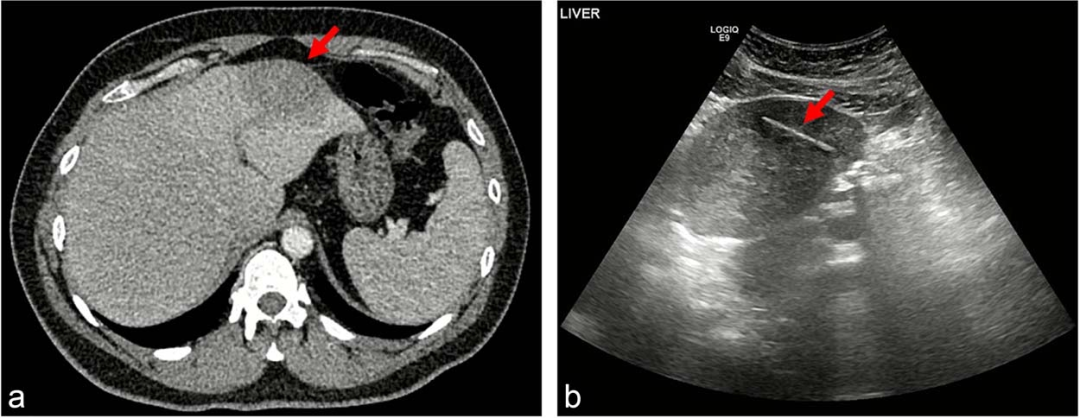

图1 (a) 肝左叶低密度灶;(b) 低回声灶内线状低回声结构

门诊随访超声检查以评估脓肿消退情况时,结果显示肝内有一个4cm线状低回声结构(图1b),怀疑存在异物。进一步追问病史得知患者在本次入院前数周,进食时不慎折断鸡尾酒签尖端咽下并出现腹痛,随后在当地就诊时患者一般情况良好,